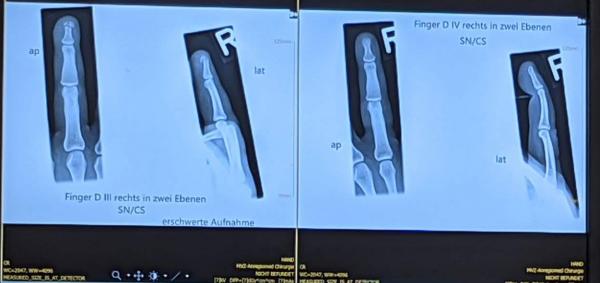

Ich habe es nämlich gestern noch geschafft, meine Finger wo hinzutun, wo sie nicht hätten sein sollen. Resultat: derbe Quetschungen an Mittel- und Ringfinger sowie eine gebrochene Mittelfingerspitze.

20210617_autsch.jpg